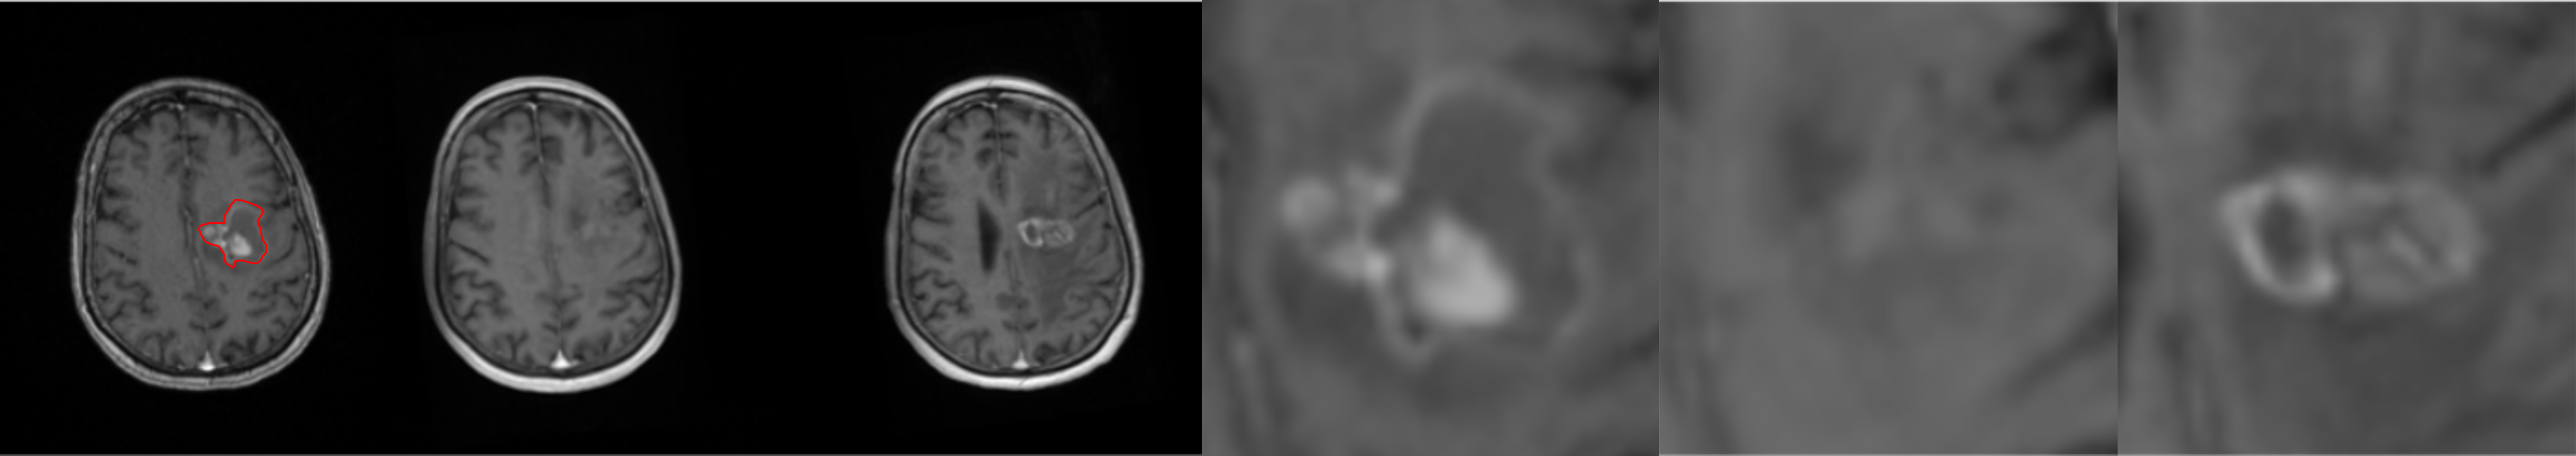

To further illustrate the model’s performance we retained only the pred 2-class model, as it reflects a realistic use case. We present several generated examples in Fig. 4. The first row corresponds to the highest local SSIM score (0.71), depicts a patient who underwent total resection, where tumor progression is minimal. We observe that the model fails to predict the hyper-intensity in the periphery of the tumor (T1-enhancement) in comparison to the ground truth. In contrast, the last row corresponds to the lowest SSIM score (0.02), making it an edge case. We observe that the model generally failed to predict T1-enhancement localized to the tumor area; however, it succeeded in predicting the necrotic area.